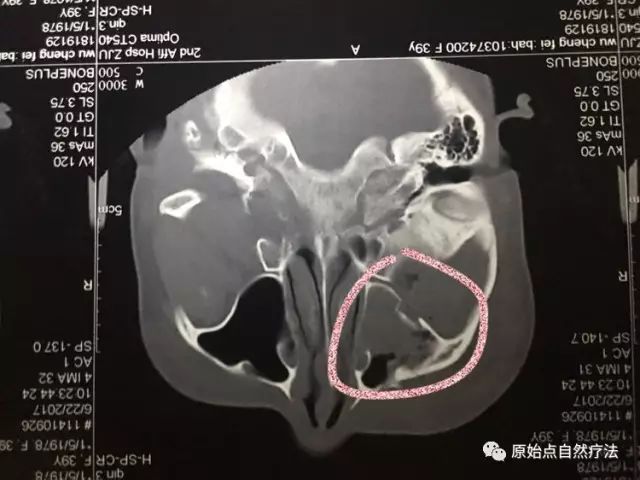

- 影像所示:右上颌窦前外壁及右眼眶外侧多发骨折,碎骨片形成,右侧颌面部软组织肿胀、积气伴血肿形成:左側颌面部軟組織稍腫脹。

- 右眼眶骨折

- 右眼眶外側壁多發骨折,碎骨片形成。

影像所示:右上颌窦前外壁及右眼眶外侧多发骨折,碎骨片形成,右侧颌面部软组织肿胀、积气伴血肿形成:左側颌面部軟組織稍腫脹。

右眼眶骨折

右眼眶外側壁多發骨折,碎骨片形成。

积氣伴血腫形成